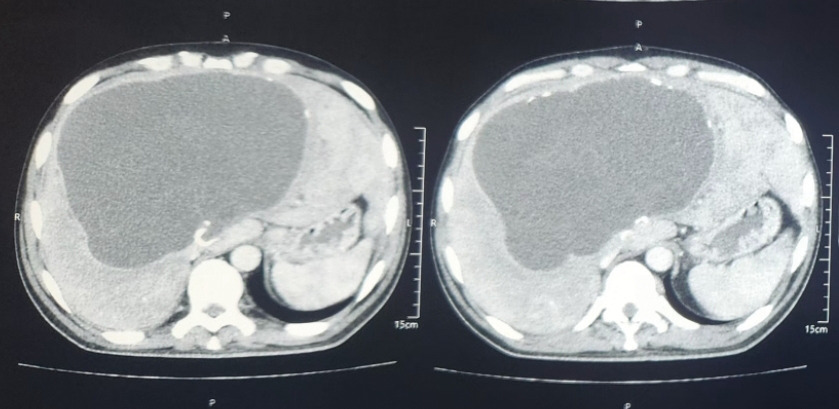

Un homme de 39 ans, originaire d'un milieu rural, sans antécédent personnel ou familial, consulte pour une douleur abdominale avec ictère. À l’examen clinique, on note la présence d’une sensibilité et d’une masse au niveau de l’hypochondre droit. Le reste de l’examen clinique est sans particularités. Le diagnostic de kyste hydatique hépatique géant est retenu à la suite de la réalisation d’une tomodensitométrie abdominale (figure). La sérologie hydatique est positive. La prise en charge thérapeutique a consisté en une résection chirurgicale, puis en un traitement médical par albendazole. L’évolution a été favorable.

Le kyste hydatique du foie est une maladie parasitaire causée par le développement intrahépatique d’Echinococcus granulosus. Cette pathologie reste courante et représente un enjeu de santé publique dans les régions à forte endémie, telles que les pays du bassin méditerranéen et l’Afrique du Nord. Le diagnostic se fait sur l’imagerie, l’échographie associée au Doppler étant l’examen privilégié. Le scanner est recommandé lorsqu’il existe des difficultés diagnostiques à l’échographie, notamment en présence de kystes volumineux.1 Le traitement du kyste hydatique combine des approches médicales et chirurgicales. L’objectif de la chirurgie est d’éliminer l’obstacle causé par le kyste, en procédant à une résection du dôme saillant ou à une périkystectomie. Ce geste doit être accompagné d’un traitement à l’albendazole, débuté quatre jours avant l’opération et poursuivi jusqu’à quatre semaines après, afin de prévenir la propagation du parasite et éviter les rechutes.2